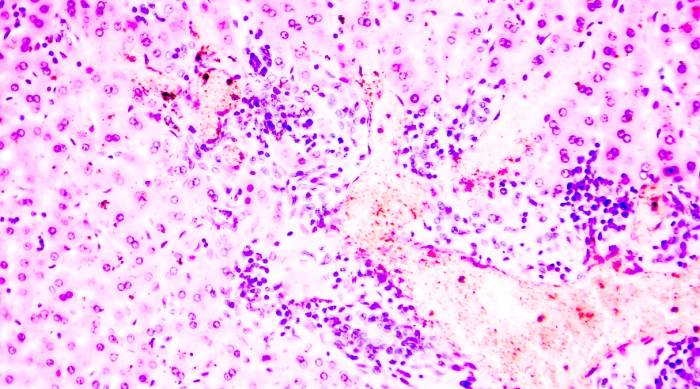

Для второй степени характерно формирование фиброзных перегородок между клетками. Изменения в паренхиме органа, характерные для данного периода, представлены на изображении (фиброзные ткани белого цвета):

В период третьей заболевания наблюдаются фибротические формирования в кровеносных сосудах железы и желчных протоках. На терминальном этапе, при переходе в форму цирроза, ткани сильно деформируется. Выявляются явные изменения в ее структуре. Видоизмененная паренхима печени выглядит так: